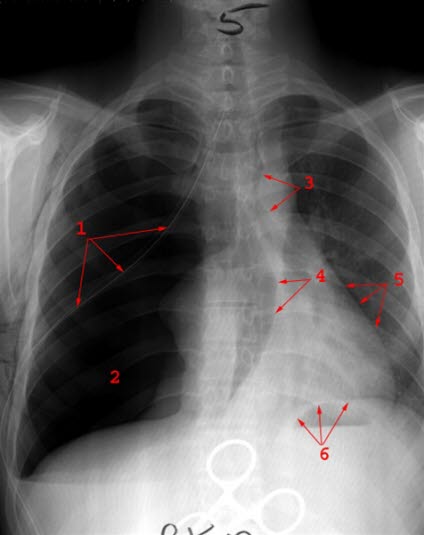

Ventilpneumothorax

Ventileffekt med betydelig overskytning av mediastinum

- Dren

- Luftfylt thorakshule

- Bronkie (pilene står en over og en under carina)

- Høyre hjerteskygge

- Venstre hjerteskygge

- Diafragma